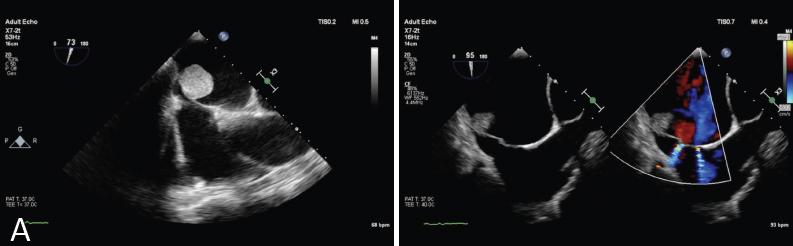

Figure 2